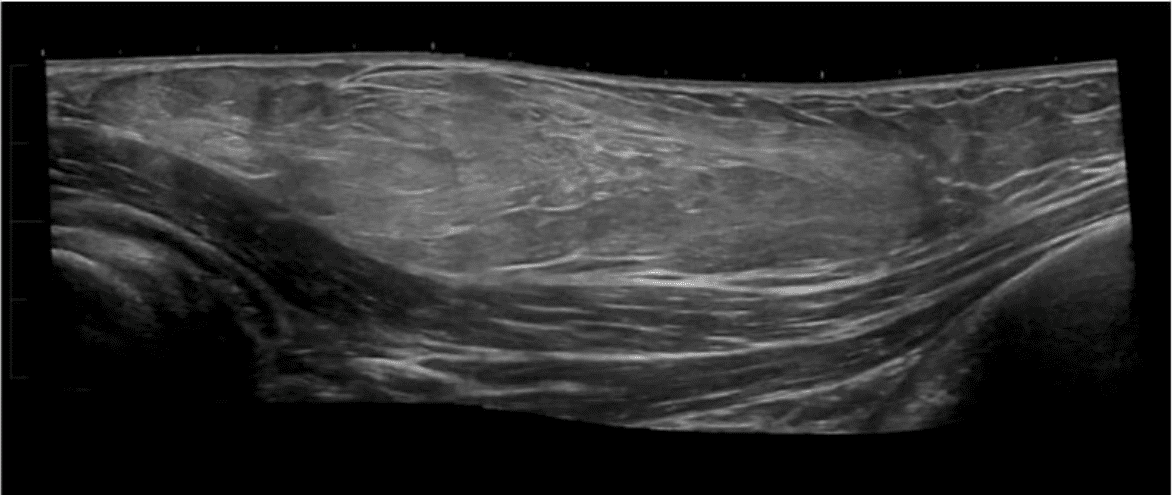

A ultrasound image of a person's body